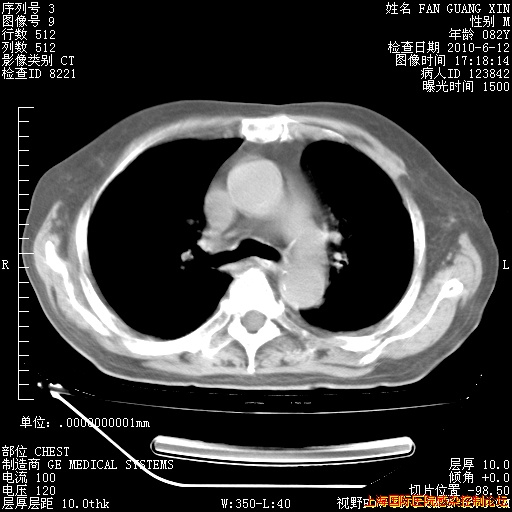

6月12日纵膈窗

整整相隔30天的肺部CT好像有所好转啊。甲强龙减量第3天,需要观察体温。

海管,自昨日你和我通完话后,不知您岳父消化道症状有无缓解?体温怎样?阅读7.12日胸部ct,个人认为目前激素治疗是有效的,甲强龙减量是适宜的。因在抗痨治疗,需密切观察肝功、肾功能和血常规。不过,老年、长期住院和大量使用激素,很担心菌群失调发生